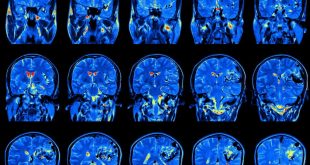

نوروسافاری| طبق مطالعه جدید محققان، افراد دارای سطح تحصیلات بالاتر بسیار در معرض ابتلا به انواع تومورهای مغزی قرار دارند. مطالعه محققان سوئدی نشان می دهد افراد دارای تحصیلات دانشگاهی، مشاغل تخصصی یا حقوق بالا بیش از افراد دارای تحصیلات پایین تر، مبتلا به تومور مغزی می شوند. …